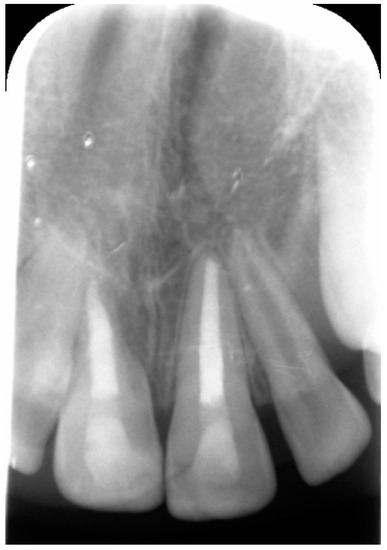

External Root Resorption Management of an Avulsed and Reimplanted Central Incisor: A Case Report

2. Case Report